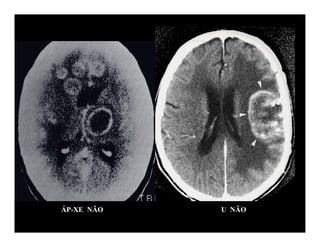

ÁP-XE NÃO U NÃO

NHỒI MÁU NÃOTỤ MÁU NGOÀI MÀNG CỨNG

• 28.